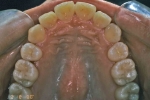

| 初診時